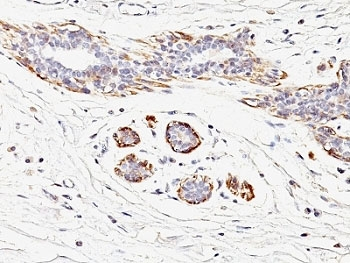

IHC: Formalin-fixed, paraffin-embedded human breast carcinoma stained with SMMHC antibody (MYH11/923).